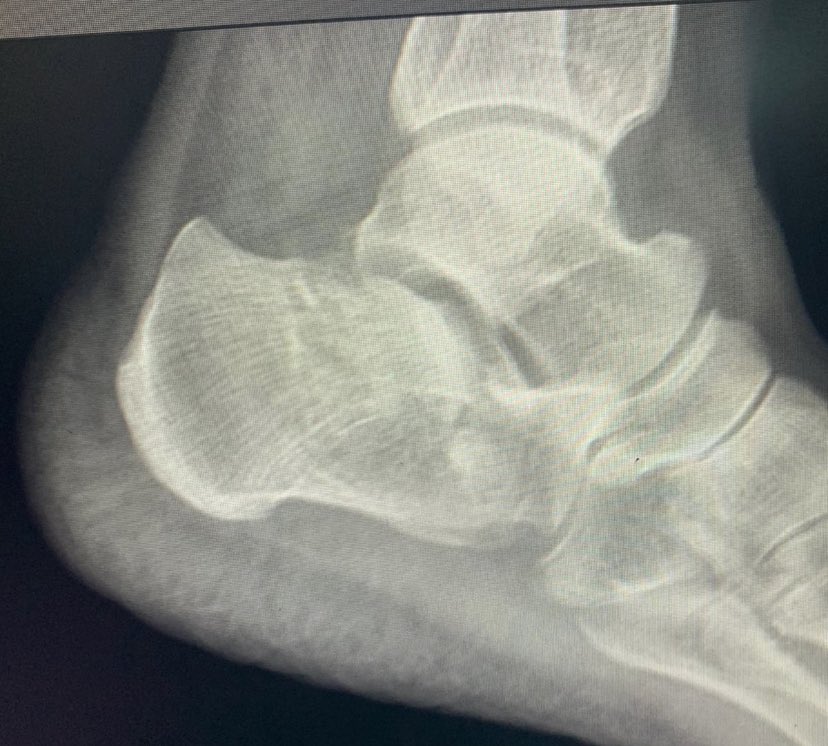

Male 40yo, healthy and physically active.

How do you treat this fracture?

Nonop, ORIF with plate or nailing?

@InvictaOrtho @traumaticum @rkh_md @Gnomelover1970 @aqueipot @DrMarecek

@DrBhavinJadav

#orthotwitter